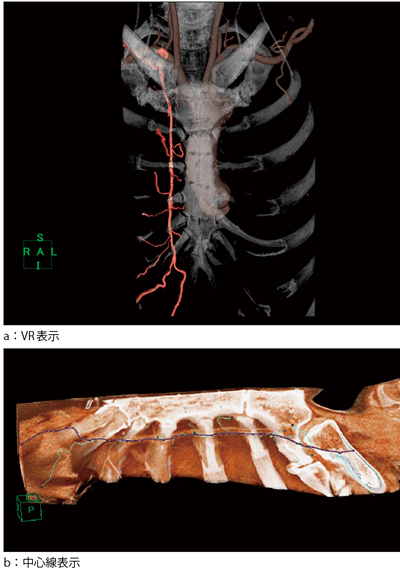

この冠動脈バイパスグラフト解析ソフトウエアは,前述のY-composite型グラフトの検出と同じ原理で,内胸動脈の分枝の検出にも活用できる。内胸動脈分枝を画像表示することで,冠動脈バイパス術で最も多く使用される内胸動脈グラフトの剥離をサポートする。内胸動脈の剥離は,制限視野下に脆弱な分枝を処理するが,最近頻用されるskeletonizedグラフトでは,冠動脈の解離や枝抜けによる血管壁内血腫のリスクが高くなる。術前評価で得られる詳細な分枝の位置や走行は,きわめて重要な情報となる。以下に,術前の胸部CTデータをもとに本ソフトウェアの機能を用いて内胸動脈の分枝検出を行った例を示す。

本症例では,血管内径1mm以上の分枝を自動的に認識し,内胸動脈から肋間に向けての走行を追跡できた。この血管中心線情報と胸骨近傍のvolume rendering(VR)データを重ね合わせて表示することで,内胸動脈とその分枝がどのように走行するかを非侵襲的に知りうる(図3 a,b)。このような表示方法は,血管の中心線を解析して表示することで可能となる。

図3 内胸動脈の分枝検出